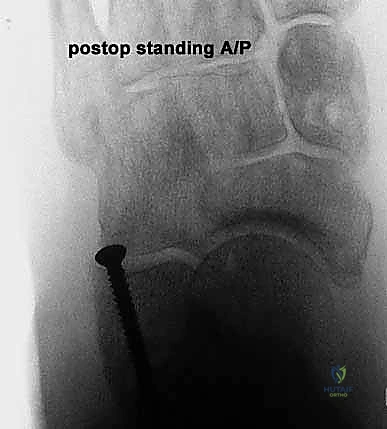

* الأشعة السينية (X-rays) مع تحمل الوزن: ضرورية لتقييم درجة انهيار القوس وزوايا العظام (مثل زاوية تالونافيكولار Meary's Angle).